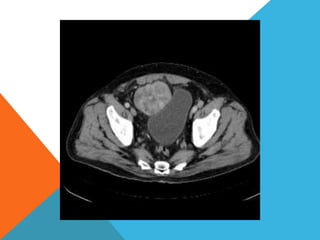

El paciente presentó síntomas de sangrado digestivo y pérdida de peso. Exámenes revelaron gastritis crónica asociada a H. pylori. Un tumor fue descubierto en una colonoscopia normal. La cirugía removió un tumor fibroide solitario, una rara neoplasia mesenquimal que usualmente crece lento y tiene bajo potencial de malignidad. El pronóstico después de la remoción quirúrgica es generalmente bueno.